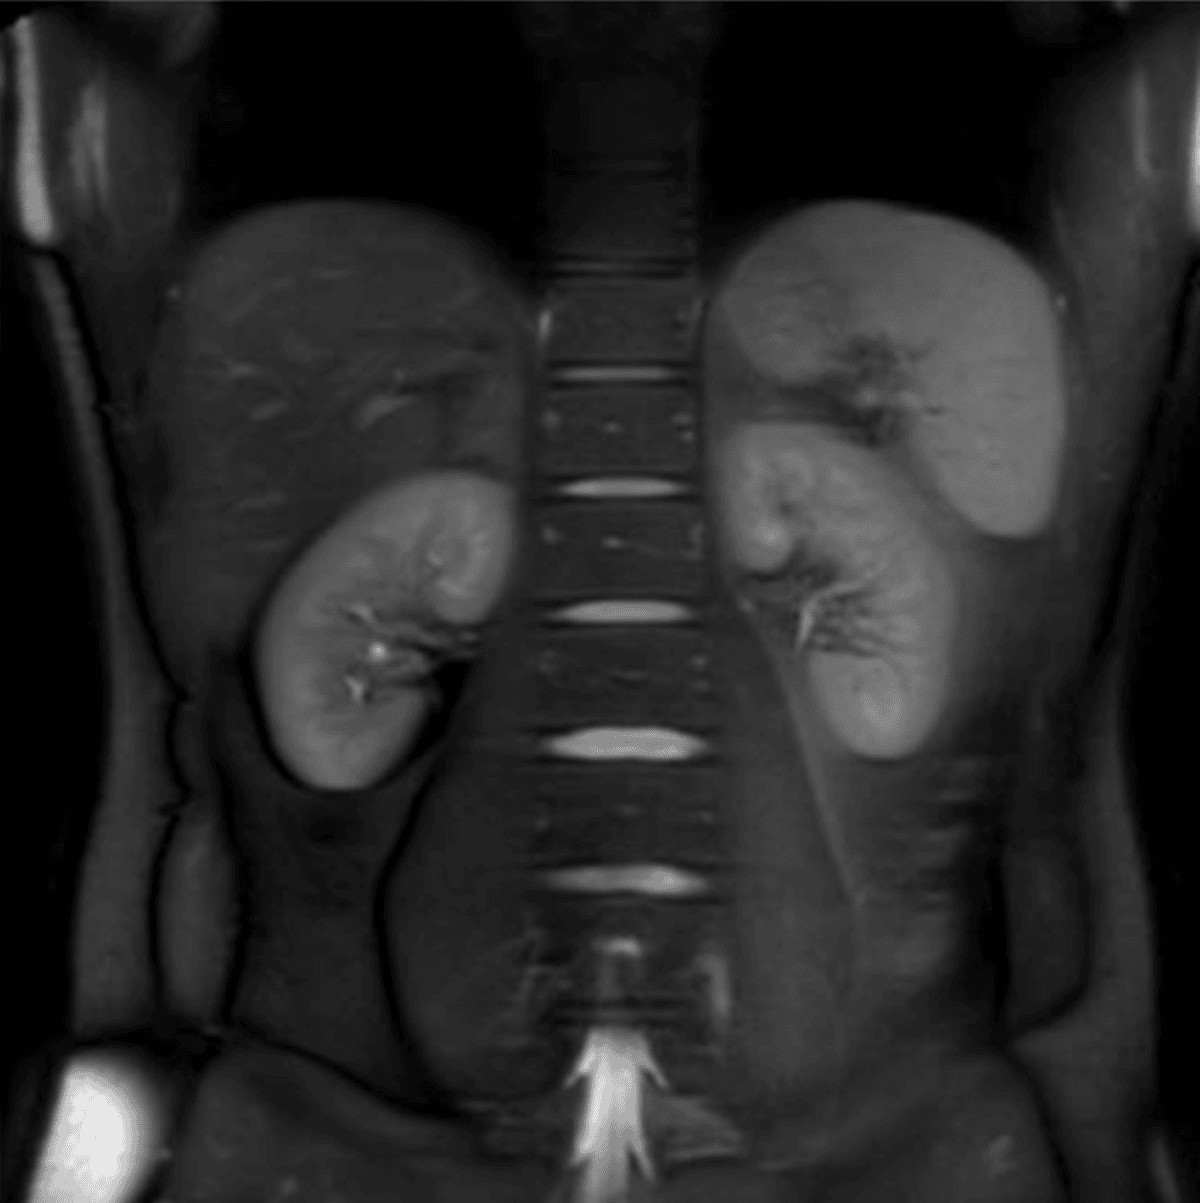

Multi-region magnetic resonance imaging (MRI) can produce images of multiple parts of the body during one MRI scan. MRIs can detect inflammation and fibrosis (fibroinflammation) in the kidneys, liver, and pancreas, can identify abnormalities that could indicate peripheral neuropathy, and can identify potential issues in many organs13,14.

The use of multi-region MRIs enables the screening for many conditions within one scan, allowing any issues to be caught early, potentially before symptoms appear.